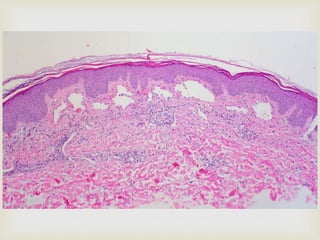

 Lymphangiomas consist of multiple intertwining

lymph vessels in a loose fibrovascular stroma

 UNENCAPSULATED

 The lining endothelium is typically thin; contains

single layer of endothelial cells with flattened nuclei

 They usually contain lymph

 Some channels may contain RBCs: likely represent

secondary hemorrhage

 In INTRAORAL TUMOURS

 Lymphatic vessels are characteristically located

beneath the epithelial surface

 They replace the connective tissue papillae: little or no

connective tissue is present between the lymph vessels

and the epithelium

 This superficial location results in the appearance of

translucent vesicle- like appearance

 Extension into deeper tissues might also be seen